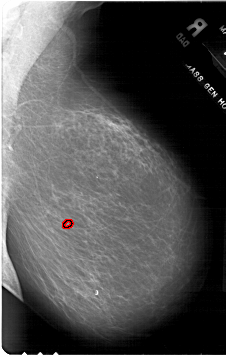

A_1773_1.RIGHT_CC

RIGHT_CC LINES 5896 PIXELS_PER_LINE 4246 BITS_PER_PIXEL 12 RESOLUTION 43.5 OVERLAY

FILE: A_1773_1.RIGHT_CC.OVERLAY

TOTAL_ABNORMALITIES 1

ABNORMALITY 1

LESION_TYPE CALCIFICATION TYPE PLEOMORPHIC DISTRIBUTION CLUSTERED

ASSESSMENT 4

SUBTLETY 2

PATHOLOGY BENIGN

TOTAL_OUTLINES 1

BOUNDARY